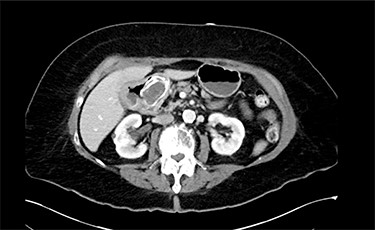

On physical exam, patient was tender in the epigastrium and right upper quadrant with no abdominal distension or peritoneal signs. Initial laboratory studies revealed white blood cell count: 8.83 K/mcl, international normalized ratio: 2.2, aspartate aminotransferase: 22 U/l, alanine aminotransferase: 19 U/l, total bilirubin 0.5 mg/dl and direct bilirubin: 0.1 mg/dl. Computed tomography (CT) scan of abdomen and pelvis showed pneumobilia with a cholecystoduodenal fistula and a large gallstone causing gastric distension proximally with no small bowel dilatation distally (Figs 1 and 2).

Abdominal CT scan (axial plane) showing gallstone in the duodenum with a cholecystoduodenal fistula.